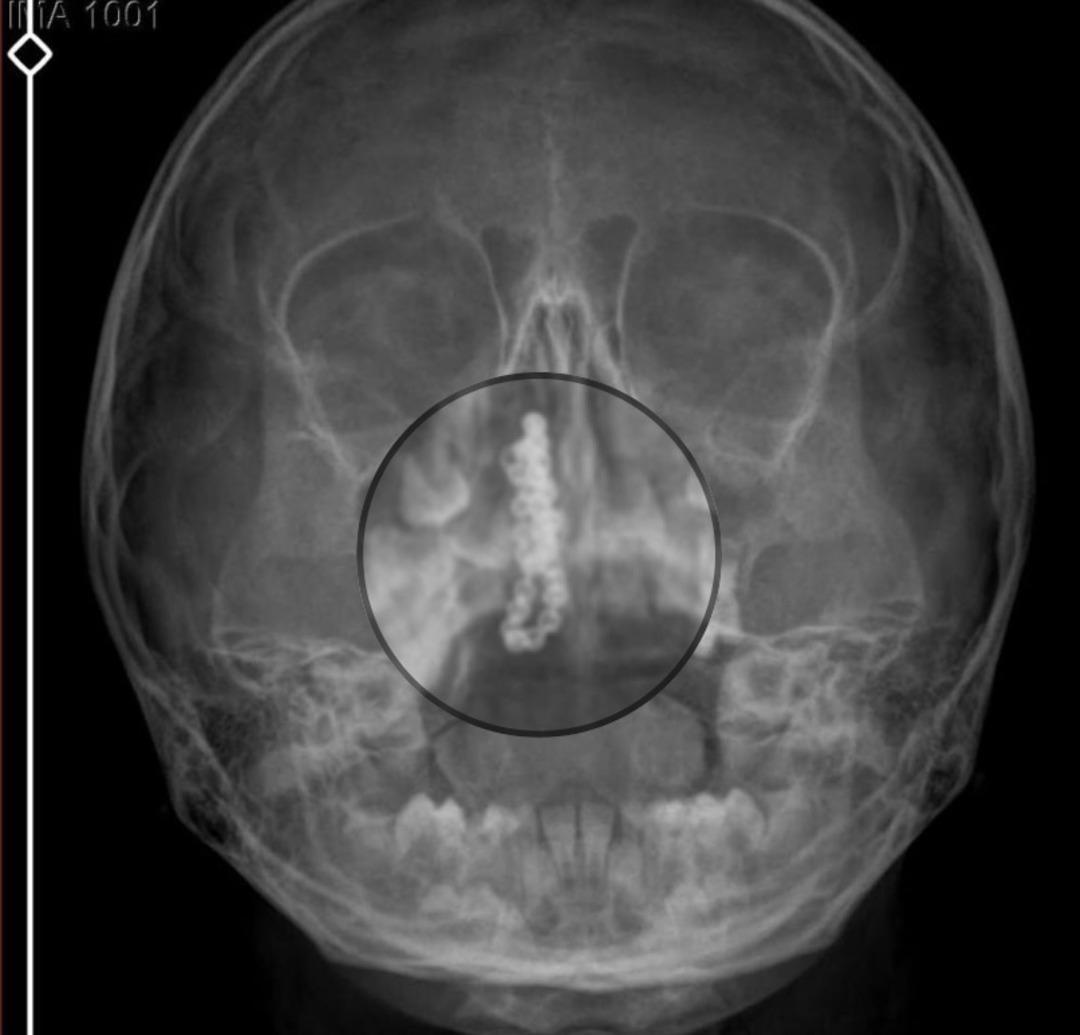

Devlet hastanesindeki doktorun incelemesi ve kapsamlı röntgen çekilmesi sonrası Polen'in burnunda metal cisim olduğu fark edildi. 2 yıldır burunda kaldığı değerlendirilip, küçük top şeklinde tırnak makası zinciri olduğu belirlenen cisim, başarılı ameliyatla çıkarıldı. Bir süre tedavisi sürdürülen Polen, sağlığına kavuşunca taburcu edildi. Özel hastane yetkilileri, konuyla ilgili açıklama yapmazken; aile suç duyurusunda bulunacaklarını söyledi.

Kızının burnundan sürekli siyah renkte akıntı olduğunu anlatan Gökhan Tekin, "Çocuğumun burnundan kanama ile sürekli siyah akıntı geliyordu. Özel hastaneye götürdüm. Özel hastanede film çekildi, hiçbir bulguya rastlanılmadığı söylendi. O siyah leke de enfeksiyona dayalı olan bir şey olduğu bize söylendi. Eve geldik, akıntı sürmesi üzerine bu kez devlet hastanesine başvurduk. Burunda metal zinciri fark ettiler.

Böyle bir ihmalkarlık olabilir mi? Özel hastaneye gidiyoruz, paramızla rezil oluyoruz. Zincir, 2 yıldır burnunda ve devletimizin hastanesinde iyi bir doktorumuz zinciri ortaya çıkarıyor, kızım ölümden dönüyor. Ben sonuna kadar bu işin peşini bırakmayacağım. Sonuna kadar hukuk mücadelesi vereceğim. Bu da diğer hastalarımıza ibret olsun. İşte, bakın koca bir zincir. 'Bulguya rastlanılmadı' deniliyor" dedi.

Kızının ameliyat sonrası durumunun iyi olduğunu söyleyen Tekin, "İnanır mısınız bize 'Evde soba mı yanıyor? Acaba kömür isten dolayı mıdır bu?' dendi. Böyle bir şey olabilir mi? Ameliyattan çıkan parmağım kadar zincir. Devlet hastanesindeki doktor da 'Bu nasıl gözden kaçılabilir? Böyle bir pozisyon nasıl görülmeyebilir?' yorumunda bulundu.